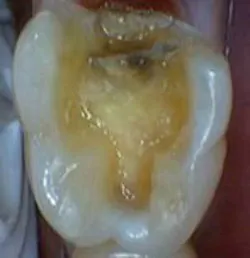

As noted in Fig. 1, the amalgam in tooth No. 19 required replacement because of marginal failure. After preparation (see Fig. 2), an image was obtained, a restoration was designed, and the CEREC restoration was seated and checked for marginal integrity (see Fig 3). Following polishing, the final restoration was seated using Variolink (see Fig. 4). Note the chameleon effect of the CEREC restoration.